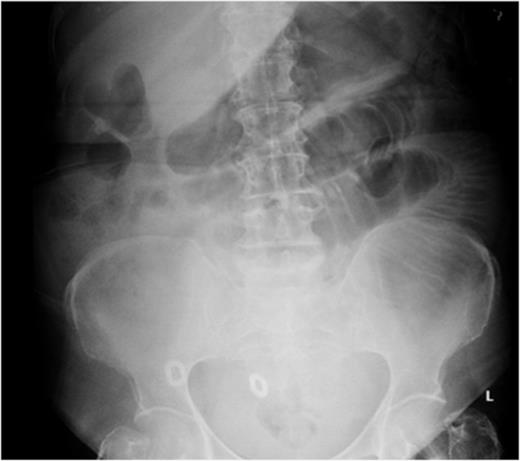

Laboratory investigations revealed an International Normalized Ratio (INR) of 10; she was anticoagulated with warfarin due to her atrial fibrillation. Initial imaging revealed dilated small-bowel loops on abdominal radiograph (Fig. 1).

Abdominal radiograph showing dilated small-bowel loops (Case 1).